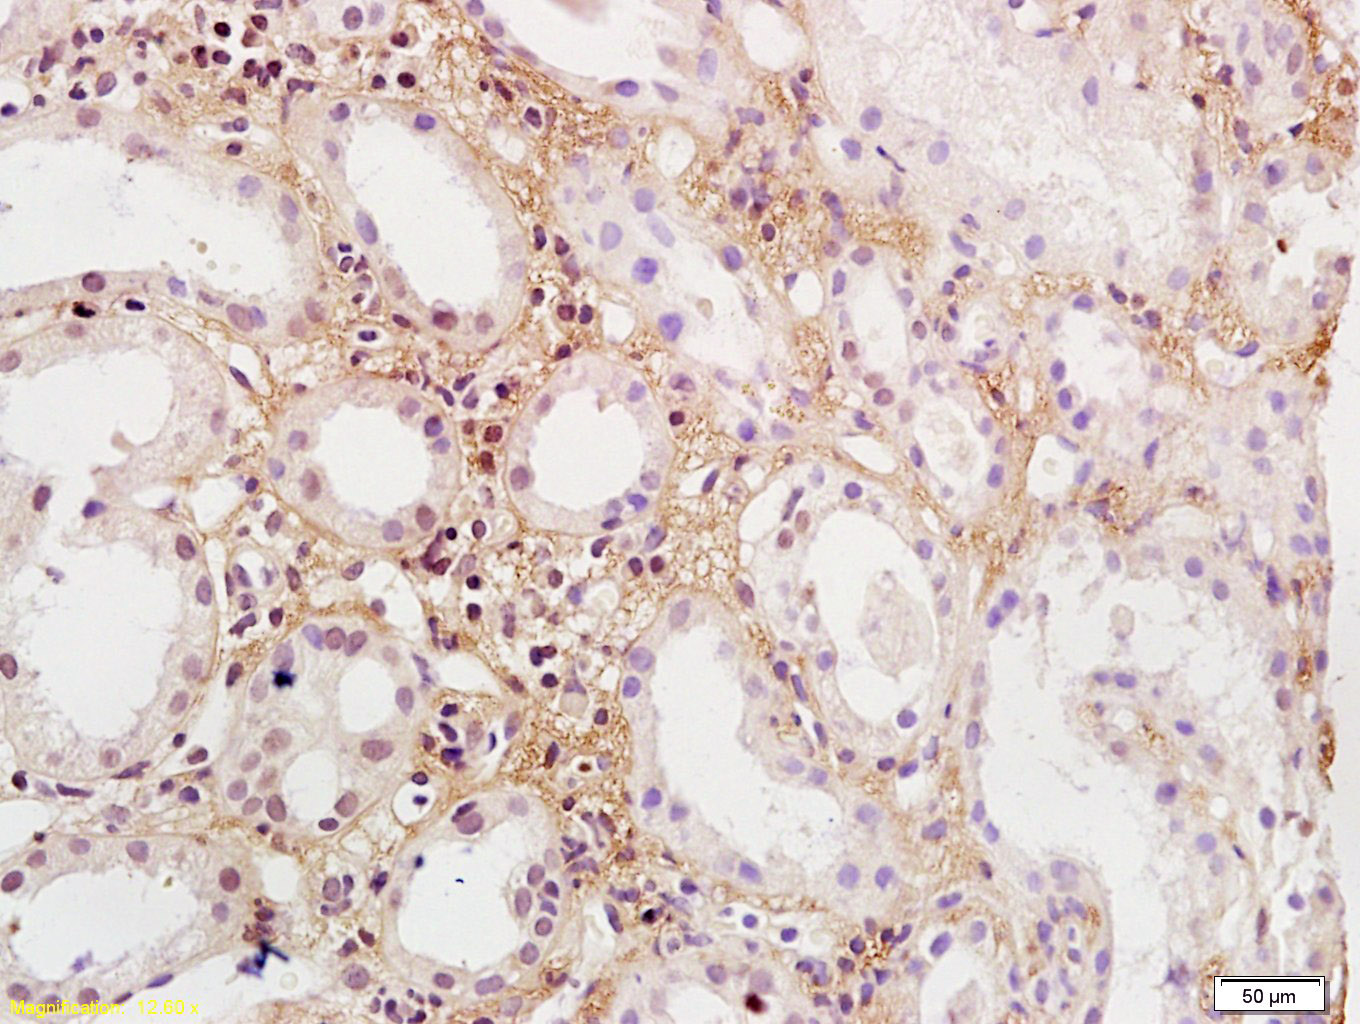

Tissue/cell: rat kidney tissue; 4% Paraformaldehyde-fixed and paraffin-embedded; Antigen retrieval: citrate buffer ( 0.01M, pH 6.0 ), Boiling bathing for 15min; Block endogenous peroxidase by 3% Hydrogen peroxide for 30min; Blocking buffer (normal goat serum,C-0005) at 37℃ for 20 min; Incubation: Anti-PDGF-BB Polyclonal Antibody, Unconjugated(bs-1316R) 1:200, overnight at 4°C, followed by conjugation to the secondary antibody(SP-0023) and DAB(C-0010) staining